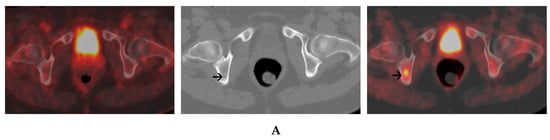

Figure 4.

A 56-year-old female with IgG kappa MM. 18FDG PET/CT (left panel) and 18F-Choline PET/CT (right panel) were performed with a 3-day-interval. An axial PET/CT image of the pelvis shows a focal uptake of 18F-Choline within the right ischium without a corresponding uptake on 18FDG PET/CT. The corresponding axial CT image (central panel) shows no clear-cut structural changes (A). A focal lesion of the right femur exhibits a high uptake of 18F-Choline. This lesion exhibits only a faint uptake on 18FDG PET/CT (left panel) and is not visible on CT (central panel) (B).